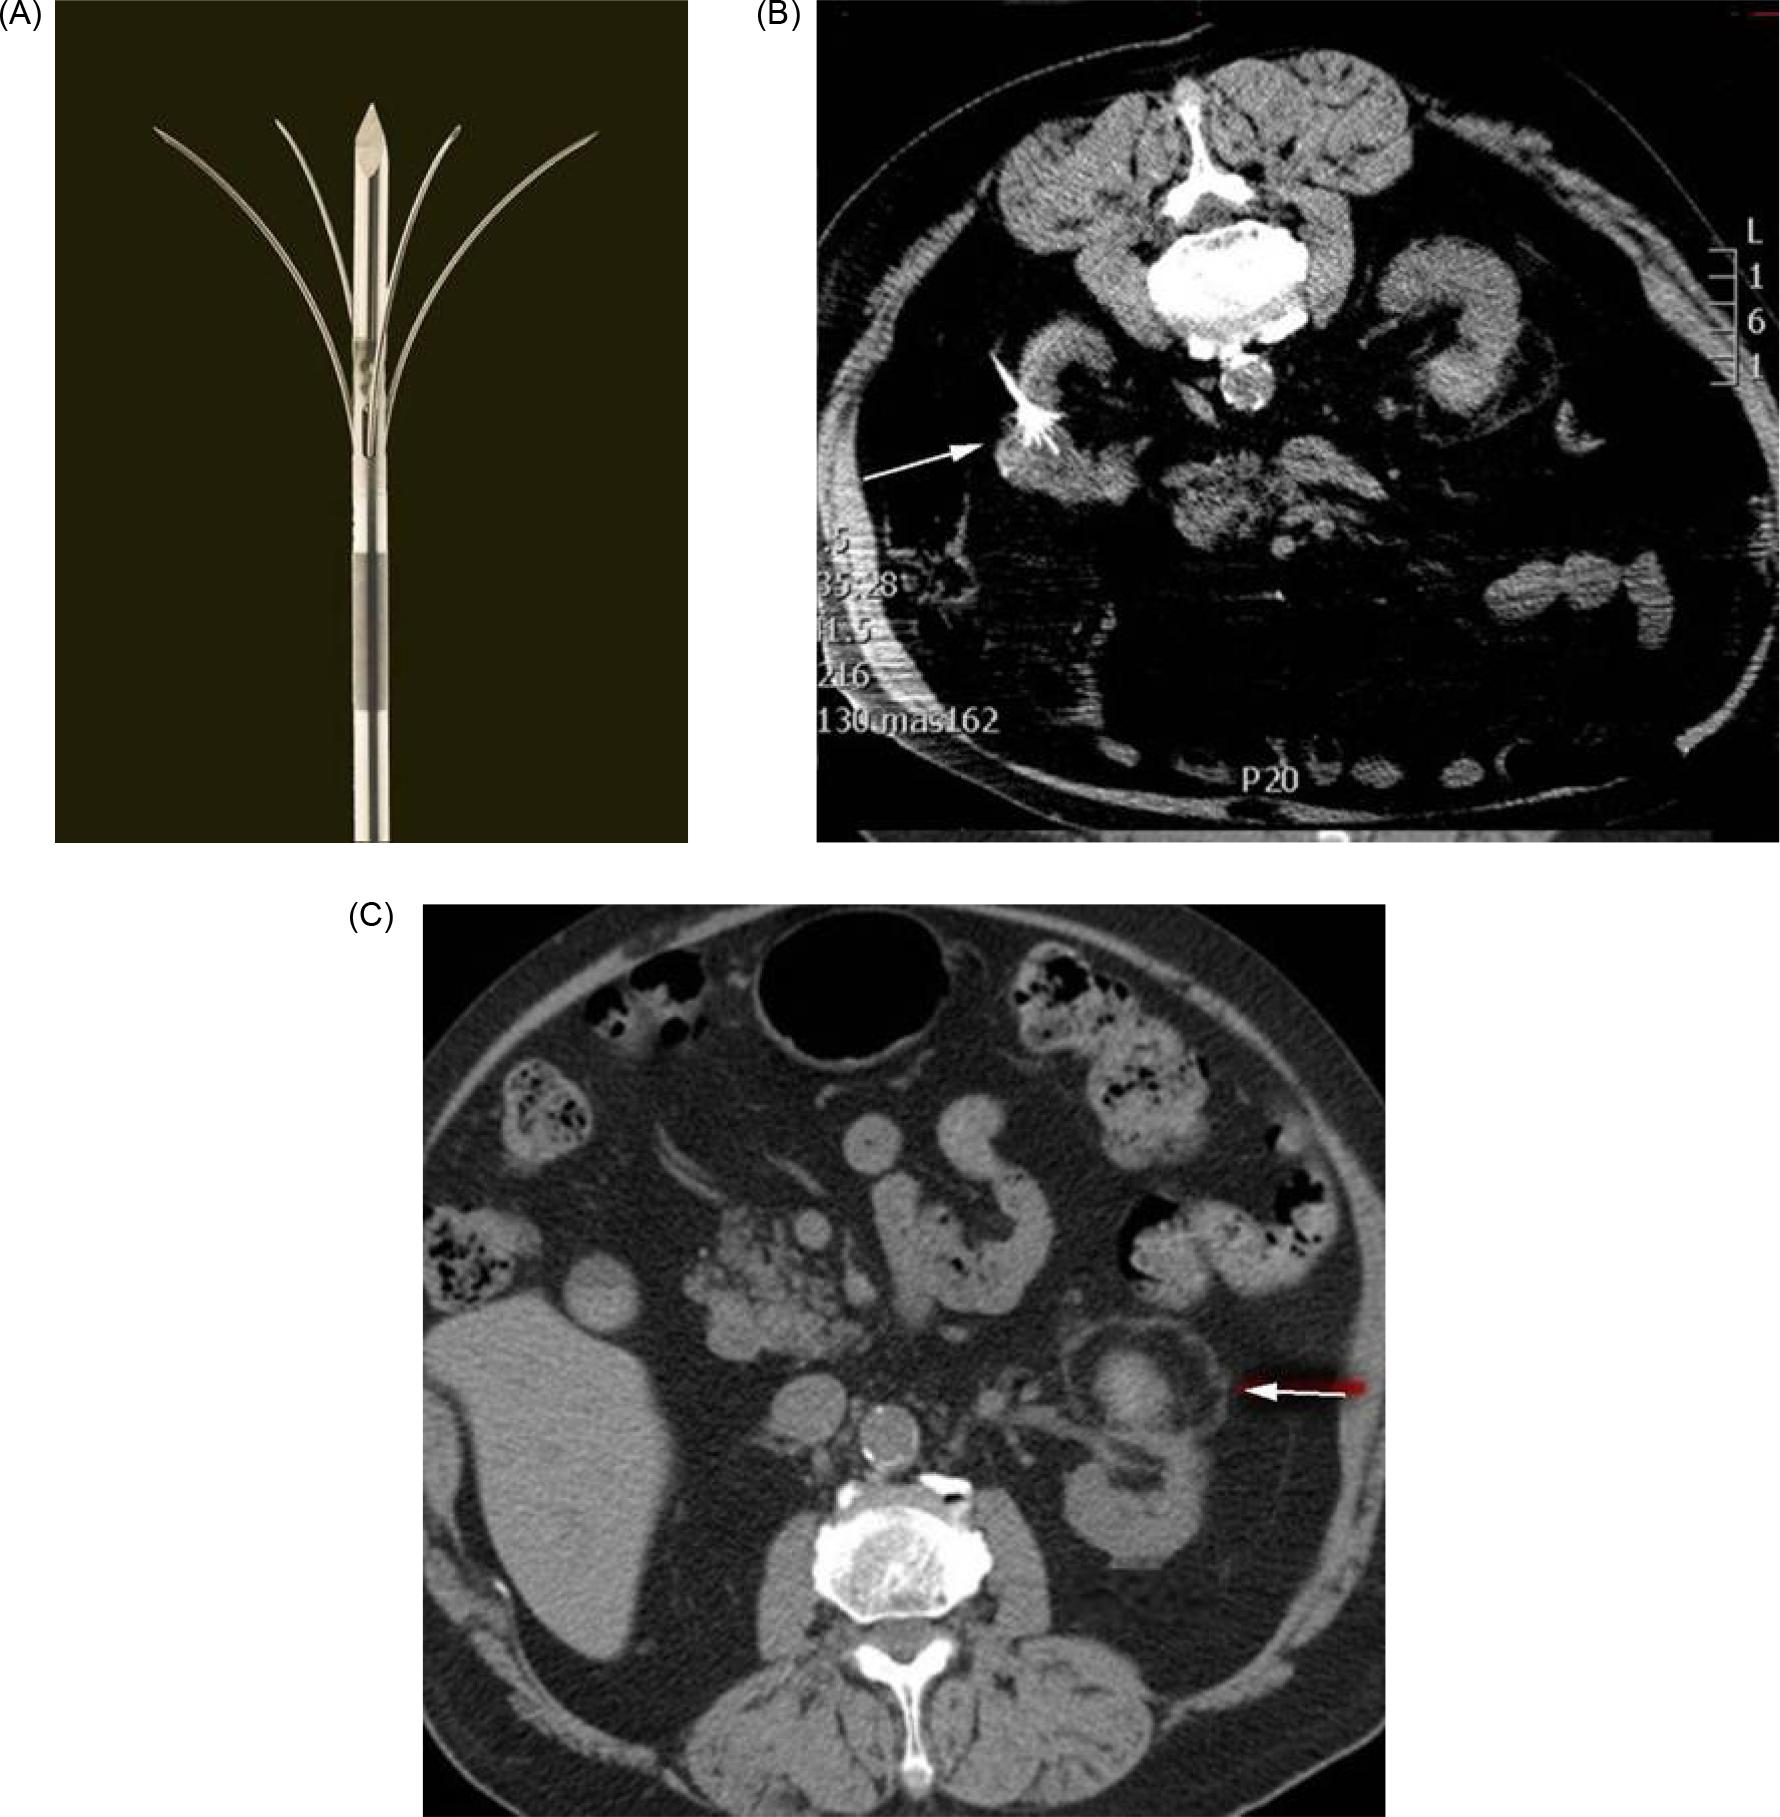

In cryoablation, the tumor is cooled to a temperature sufficient to obtain cell necrosis. Cryogen gas (typically argon) is depressurized, causing a decrease in temperature at the tip of an antenna—a phenomenon termed the Joule–Thomson effect. Through the tip of the antenna, passive thermal diffusion acts on tumor cells. Intracellular and extracellular crystals are produced by slow and fast freezing cycles (generally two), and these cycles cause cell death through cellular dehydration, vascular thrombosis, and membrane rupture (15). While −20°C is the proven temperature at which cell necrosis occurs in cryoablation, −40°C is the typical temperature achieved in real world practice. The target temperature is obtained at least 3.1 mm inside the ice ball, with shorter distances insufficient for achieving cell death (16) (Figures 1A–1C).

Figure 1: (A) Ice ball seen on the end of cryoablation probe. (B) Ice ball seen in renal tumor during cryoablation. (C) Depiction of isotherms of ice ball.